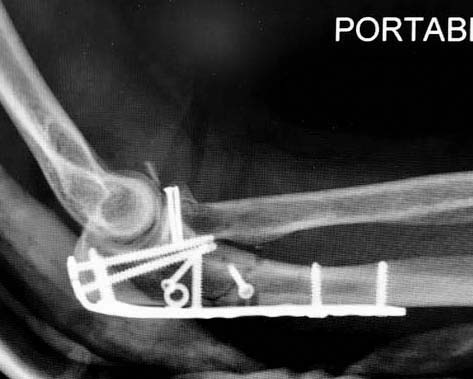

Для перелома локтевого отростка придуманы много пластин, надо выбрать по

длине. А при краевых переломах головки ее окружность можно восстановить

винтами 2 мм, но в данном случае имеется полный вывих головки и

фиксация, даже специальной пластиной, может осложнится. Протез головки

после удаления предупреждает нестабильность в суставе и деформацию оси

конечности в будущем!